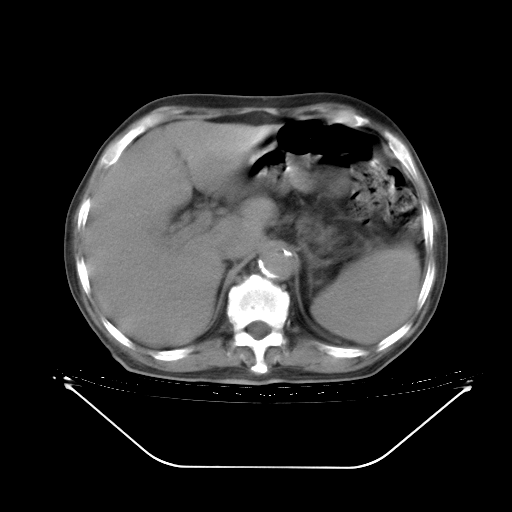

胸腹部CT,诊断意见:左上肺叶钙化灶、左侧胸膜局限性增厚并钙化、胆囊炎。描述部分肺组织呈磨玻璃样改变。